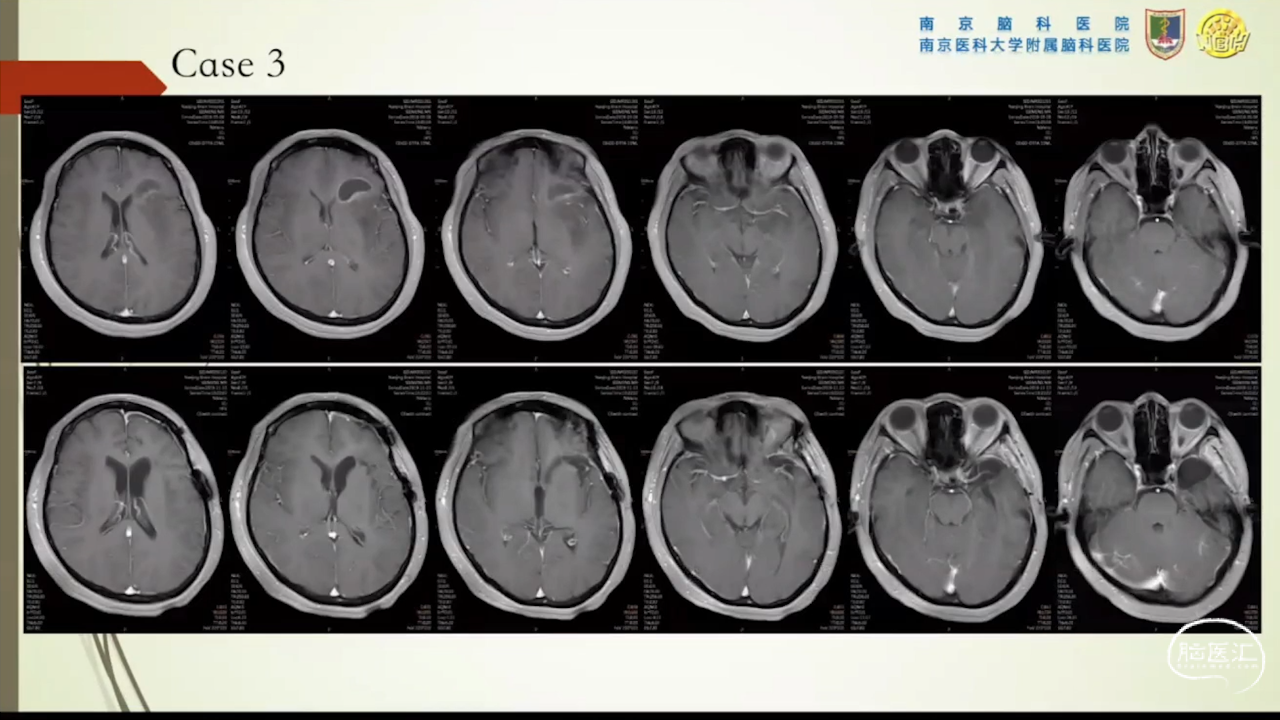

杨坤教授:岛叶胶质瘤的显微手术治疗

胶质瘤是发病率最高的颅内肿瘤(约占44.69%),岛叶是神经胶质瘤的好发部位,大约有25%的低级别胶质瘤及10%的高级别胶质瘤发生在岛叶,大多数岛叶胶质瘤为低级别胶质瘤。岛叶在调节内脏感觉运动、控制心血管交感活性、传入躯体感觉中均起重要作用。它也参与了痛觉的传递、运动规划、自主性吞咽、味觉、听觉、前庭功能、情绪、认知能力和语言能力。因为岛叶解剖结构复杂,并覆盖有高级语言皮层、白质束及重要的血管结构,故岛叶部位的手术难度极大。

讲题岛叶胶质瘤的显微手术治疗